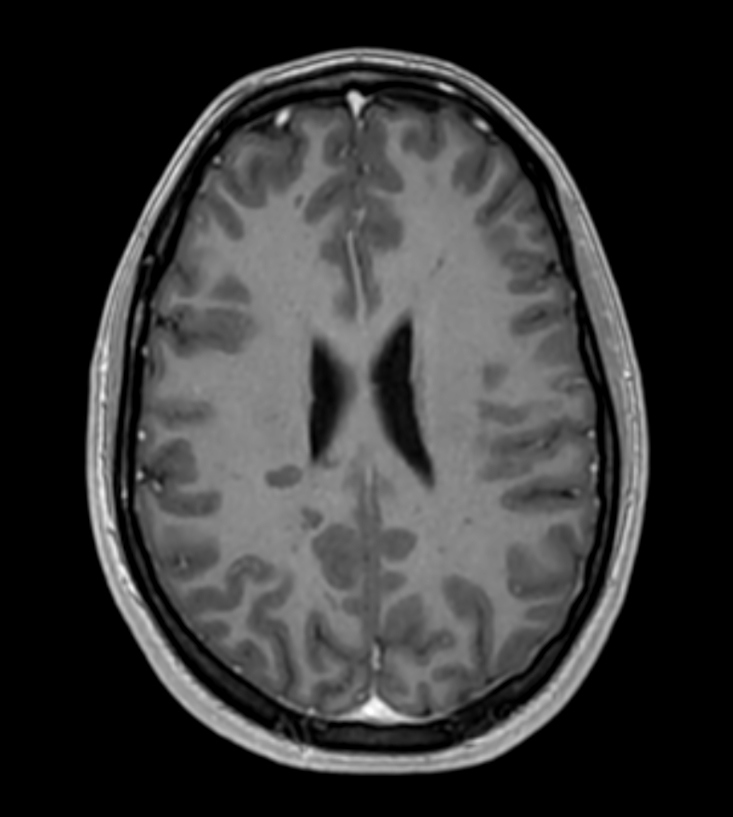

Patient with multiple brain lesions. ExamCard includes Compressed SENSE to shorten the exam time, 3D scans to acquire high resolution data in multiple directions in only one single scan and 4D-TRAK for dynamic contrast-enhanced MR Angiography enabling high spatial and temporal resolution simultaneously.

3D T1w FFE with gado Compressed SENSE